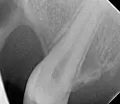

Доктор, у меня проблемы с верхними шестеркой и семеркой. Там не обойтись без протезирования, если хочу иметь зубы еще хотя бы лет 20. Но мой стоматолог рекомендует поставить не протезы, а зубной мост. Мол, это менее болезненная процедура, а при правильном подборе материалов мост ничем не выделяется из зубного ряда. Как лучше поступить: настаивать на протезировании поштучно или все-таки отдать предпочтение установке моста? И в чем его преимущества?

Добрый день. Уважаемый Максим, как для одиночных коронок, так и для мостовидного протеза есть свои показания. Преимущества отдельностоящих коронок очевидны - если с одной из них случится неприятность, вторую нет нужды снимать и в случае переделывать весь протез. В тоже время соединенные два зуба являются шинирующим элементом, если имеется патологическая подвижность одного из зубов. Поэтому советовать заочно я не могу, думаю Ваш доктор может обосновать факт предложения именно мостовидного протеза, рекомендую не стесняться расспросить подробнее Вашего врача.

На счет болезненности: эти манипуляции почти не отличаются друг от друга. Желаю Вам успехов!